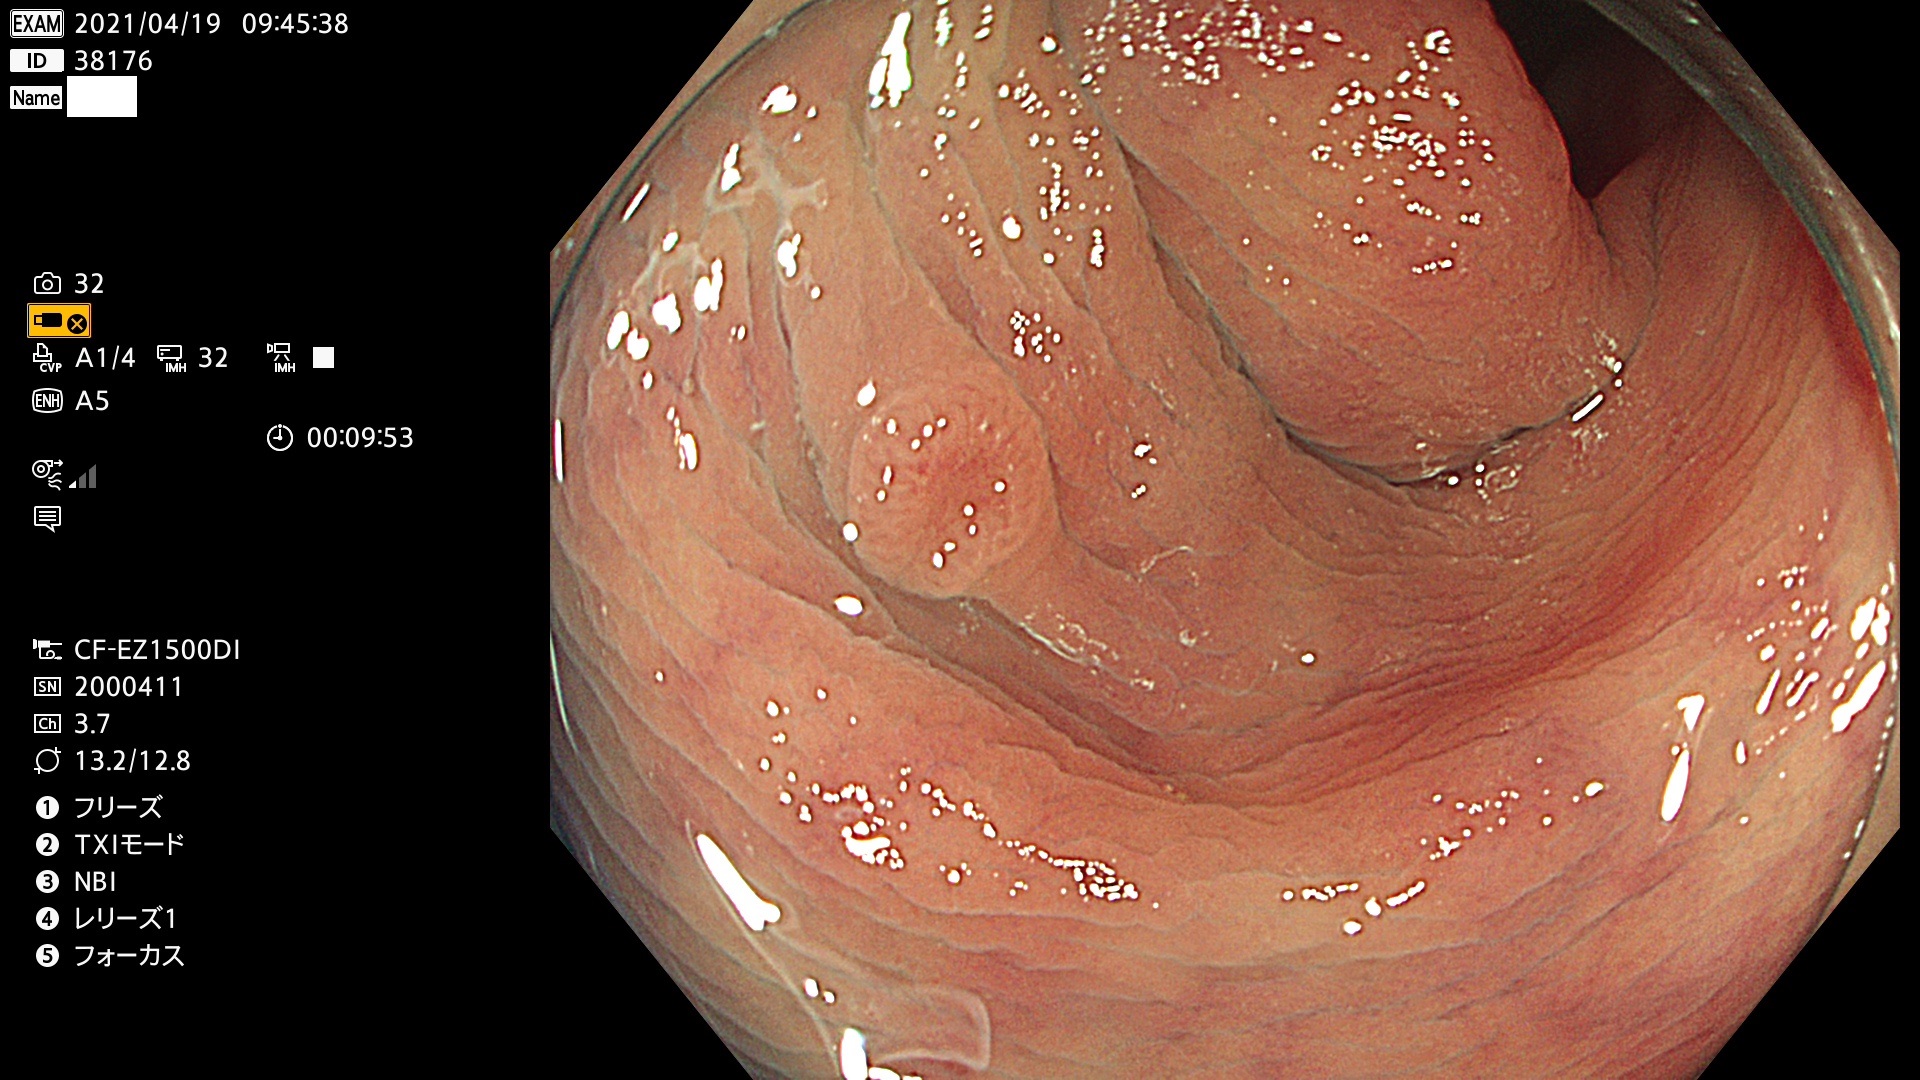

腺腫発見率 72 % (カルテ番号 38100〜38199の100名の方の検査結果で集計)大腸癌検診最新情報

以下のカルテ番号の方に腺腫(Adenoma,Group3〜5)が見つかりました(集計法)

38101 38103 38104 38106 38107 38108 38109 38110 38111 38112 38113 38114 38115 38117 38118 38122 38123 38124 38125 38126 38127 38128 38130 38131 38132 38135 38137 38138 38140 38141 38142(SSAPのみ) 38143 38144 38145 38146 38147 38148 38149 38150 38151 38152 38153 38154 38157 38158 38160 38161 38162 38164 38165 38166 38167 38168 38169 38172 38176 38177 38178 38181 38182 38183 38184 38187 38189 38190 38191 38192 38193 38194 38195 38196(SSAPのみ) 38198

発見困難で危険性の高い平坦型病変(上記100名より抽出) ![]()